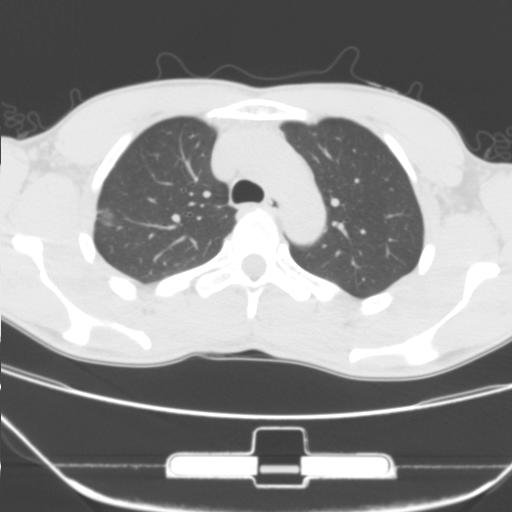

标题: CT25483:肺部病变 请指教

车祸伤者

右肺上叶后段近胸膜下结节样异常密度灶,似见分页及毛刺,考虑右肺上叶周围型肺ca,建议穿刺病理检查

周围型肺ca与炎性假瘤待鉴别。建议穿刺病理检查

缺乏病史,症状体征,但这个孤立结节具备了几乎所有的恶性征象:分叶,毛刺,空泡征,胸膜凹陷征,血管集束。